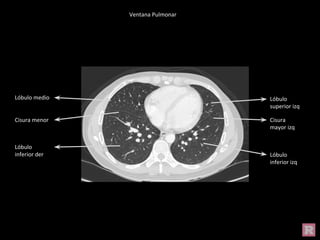

Ventana Pulmonar

Cisura

mayor izq

Lóbulo

inferior izq

superior izq

superior der

inferior der

Cisura menor

mayor der

Lóbulo medio